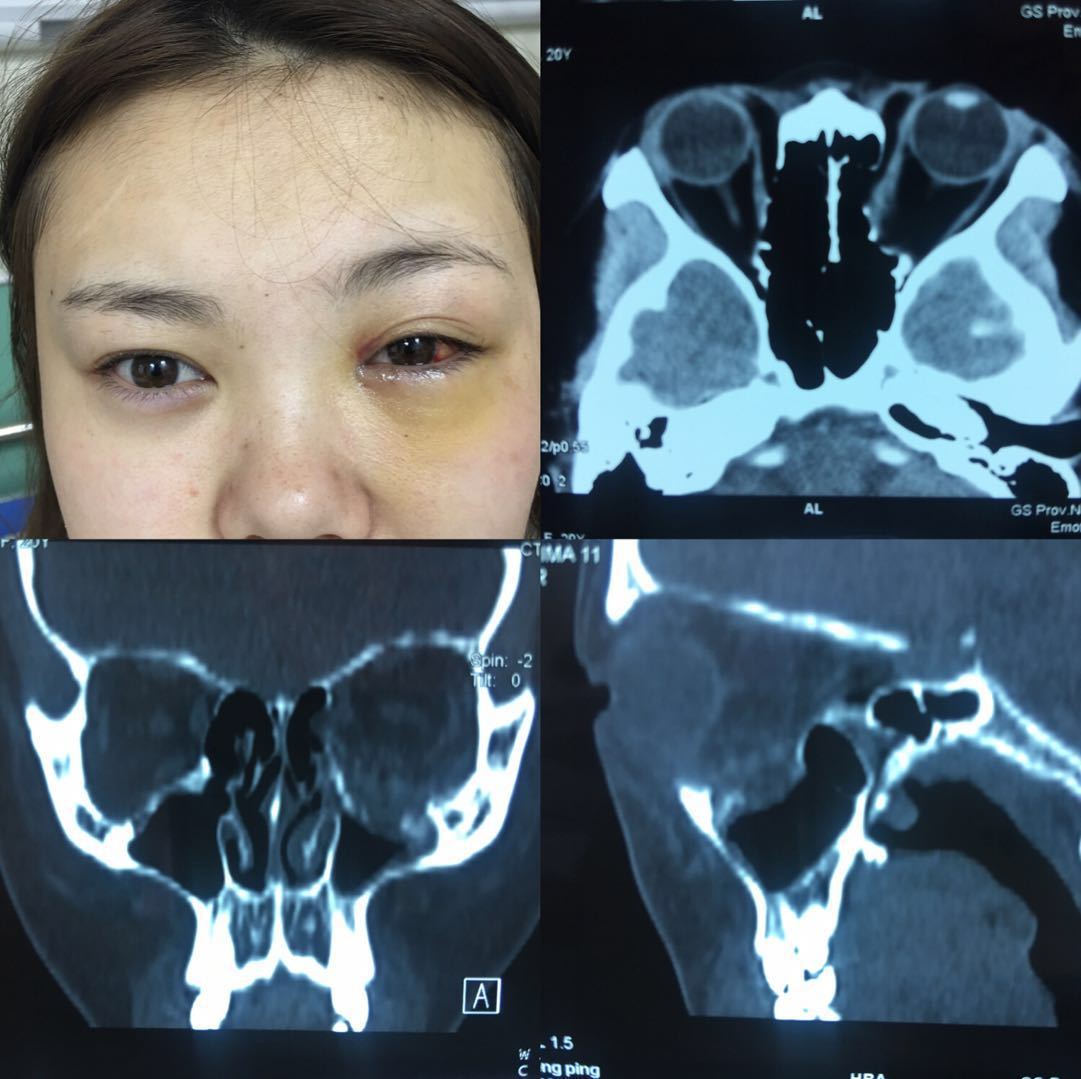

小伙车祸至左眼失明,紧急手术挽救视力.

图片尺寸1080x647